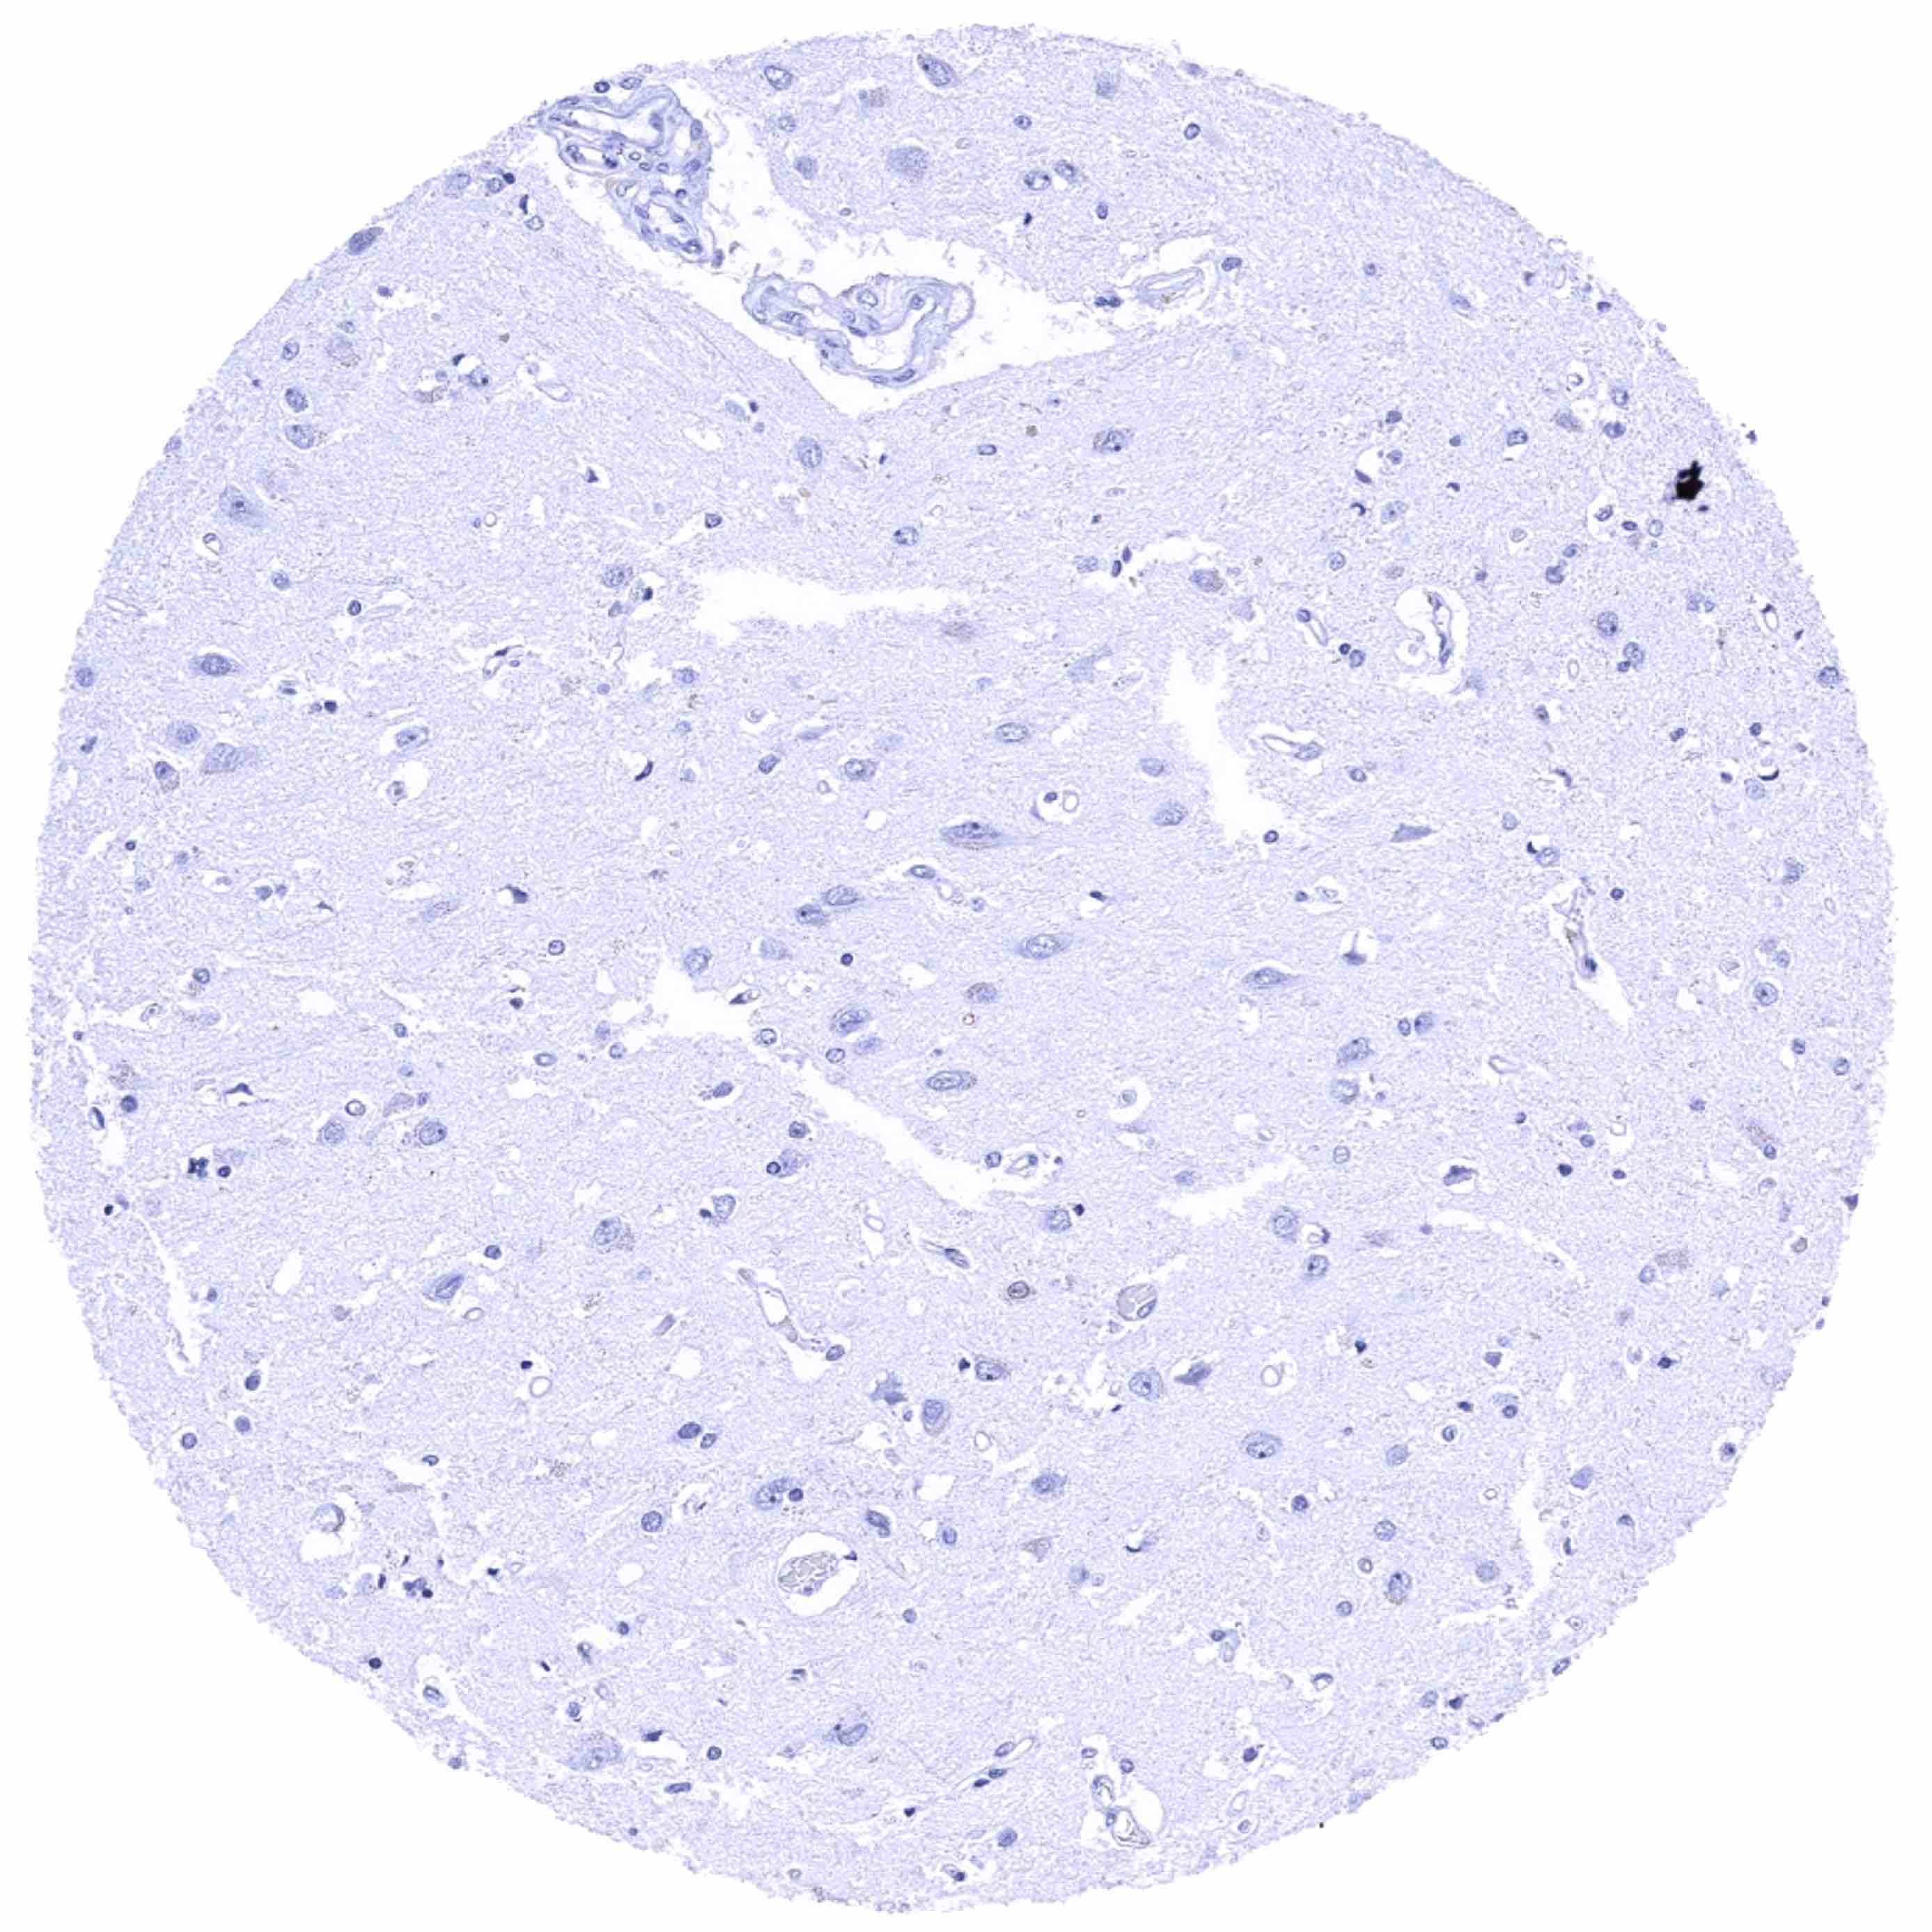

Cerebrum, grey matter